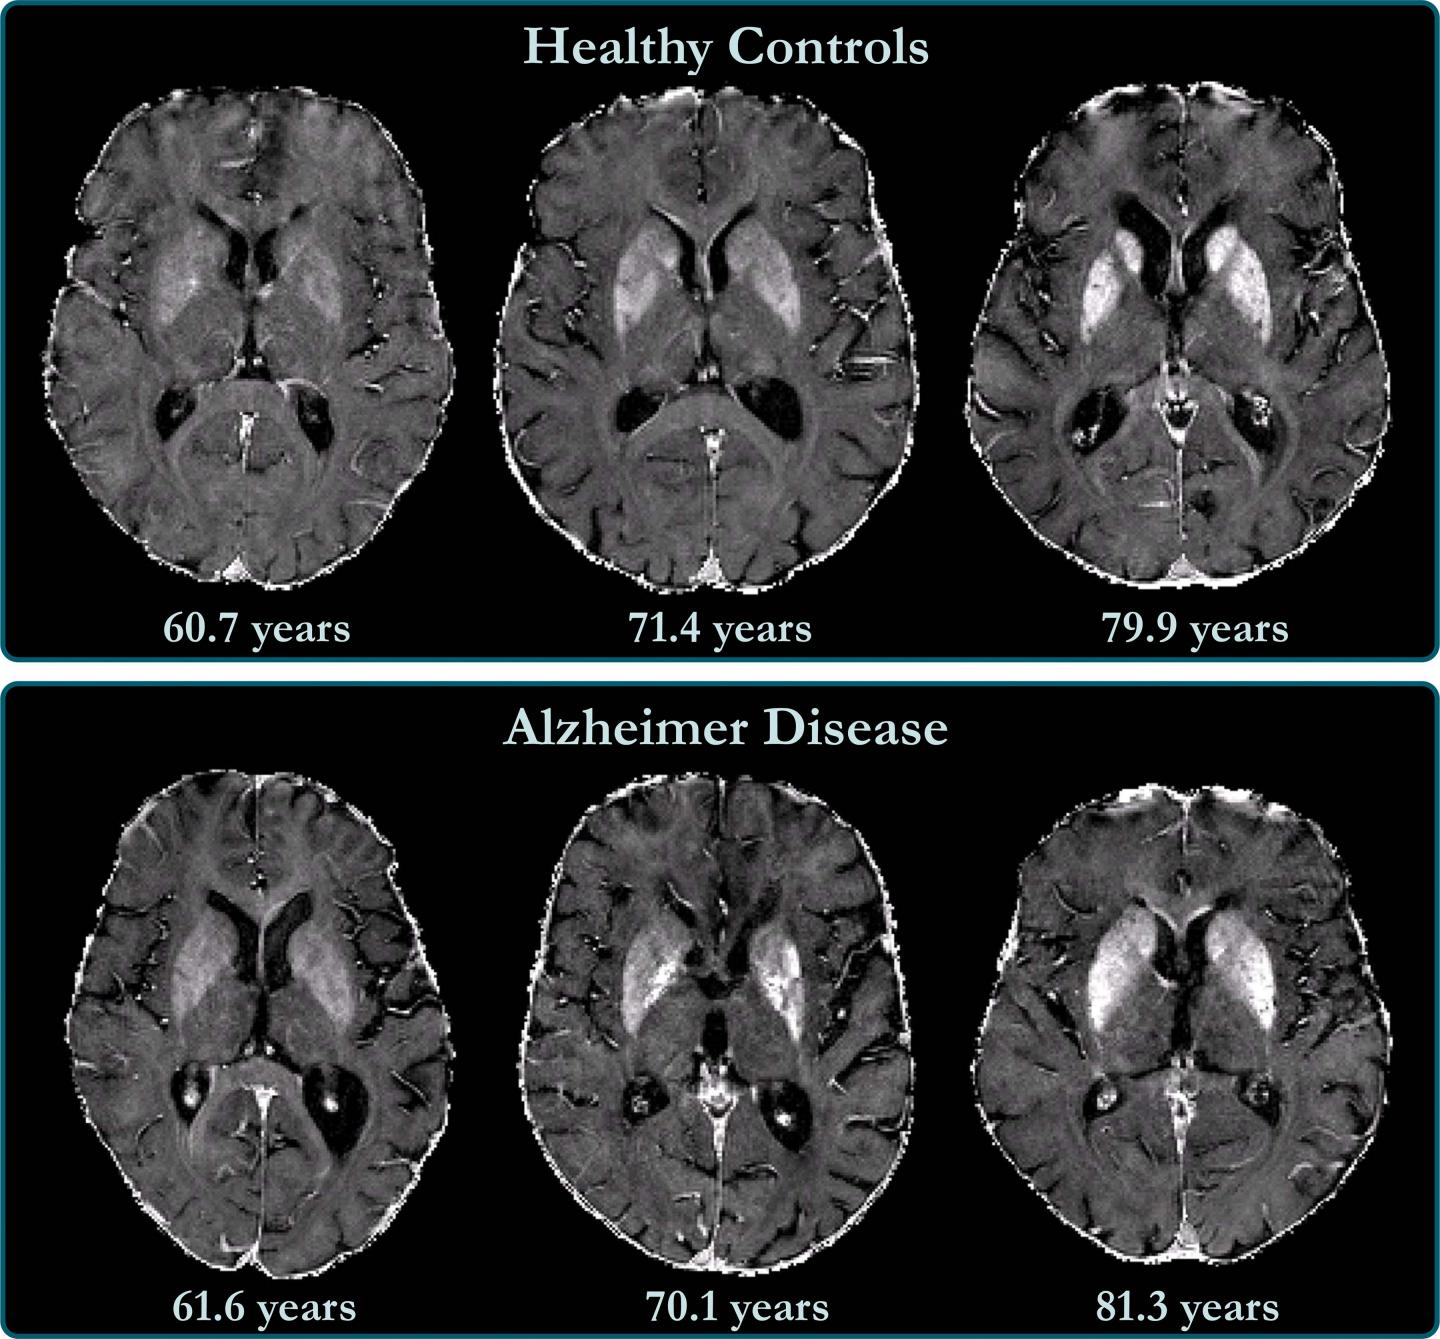

image: R2? maps of healthy control participants and participants with Alzheimer disease. R2? maps are windowed between 10 and 50 sec21. Differences in iron concentration in basal ganglia are too small to allow visual separation between patients with Alzheimer disease and control participants, and iron levels strongly depend on anatomic structure and subject age.

It is known that deep gray matter structures of patients with Alzheimer's disease contain higher brain iron concentrations. Less is known about the neocortex, the deeply grooved outer layer of the brain that is involved with language, conscious thought and other important functions. The neocortex is challenging to assess by MRI, as the anatomy of the area makes MRI prone to distortions, signal decays and artifacts.

The technique enabled the researchers to create a map of brain iron, determining iron levels in parts of the brain like the temporal lobes, or the areas of the brain lying underneath the temples, and the occipital lobes in the back of the head.

"We found indications of higher iron deposition in the deep gray matter and total neocortex, and regionally in temporal and occipital lobes, in Alzheimer's disease patients compared with age-matched healthy individuals," Dr. Schmidt said.